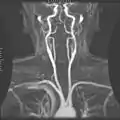

Магнитно-резонансная ангиография.

Внутренняя сонная артерия.